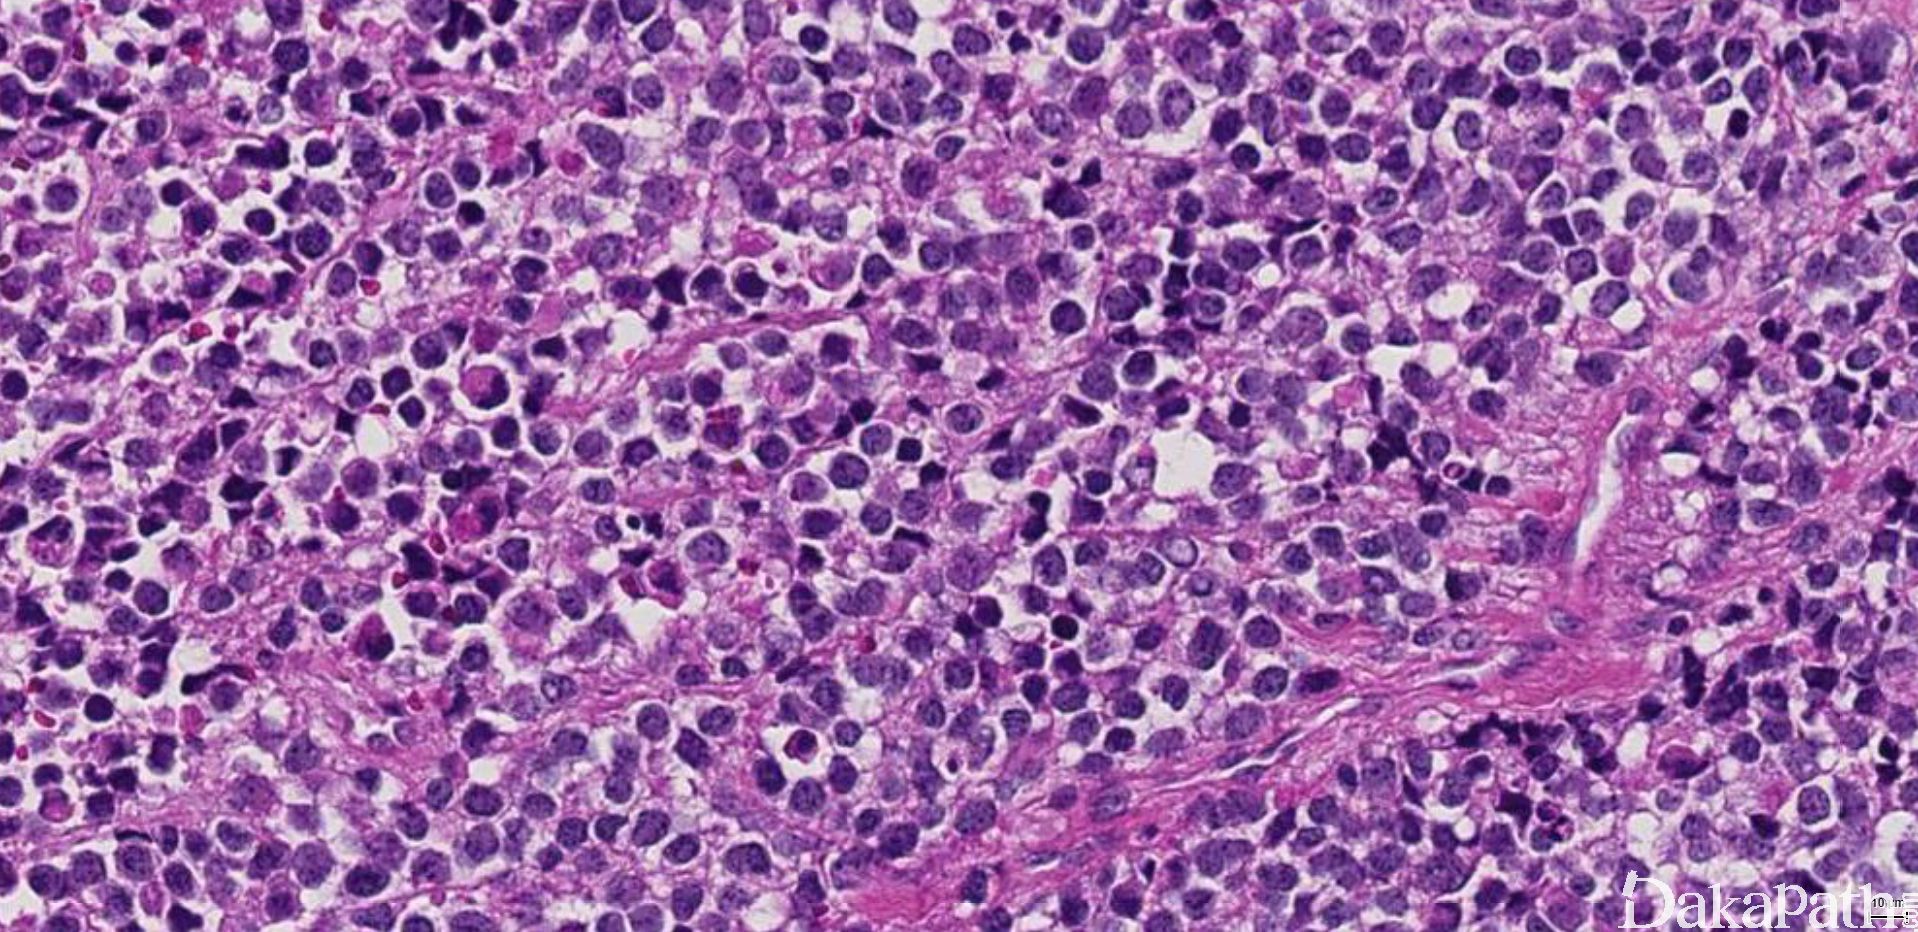

9. 实体型:

10. 由实性的瘤细胞巢组成,瘤细胞圆而较一致,具有纤细的空泡状染色质和小的核仁,部分病例瘤细胞胞质丰富而淡染或透明,类似肾透明细胞癌或软组织透明细胞肉瘤,称透明细胞变型;;

11. 仅偶见或无明显的假腺泡状结构。